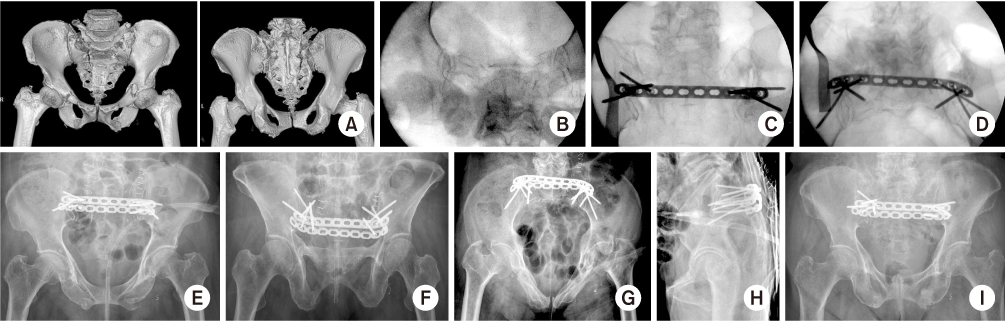

Fig. 11

(A) A 71-year-old female sustained of an unstable pelvic injury (sacral fracture). (B–D) The PTB plate fixation was performed and the osseous corridor was used to achieve the maximal screw length. (E–H) The postoperative radiographs showed an acceptable reduction of the pelvis. (I) The follow-up radiographs at 12 months showed the maintenance of reduction.